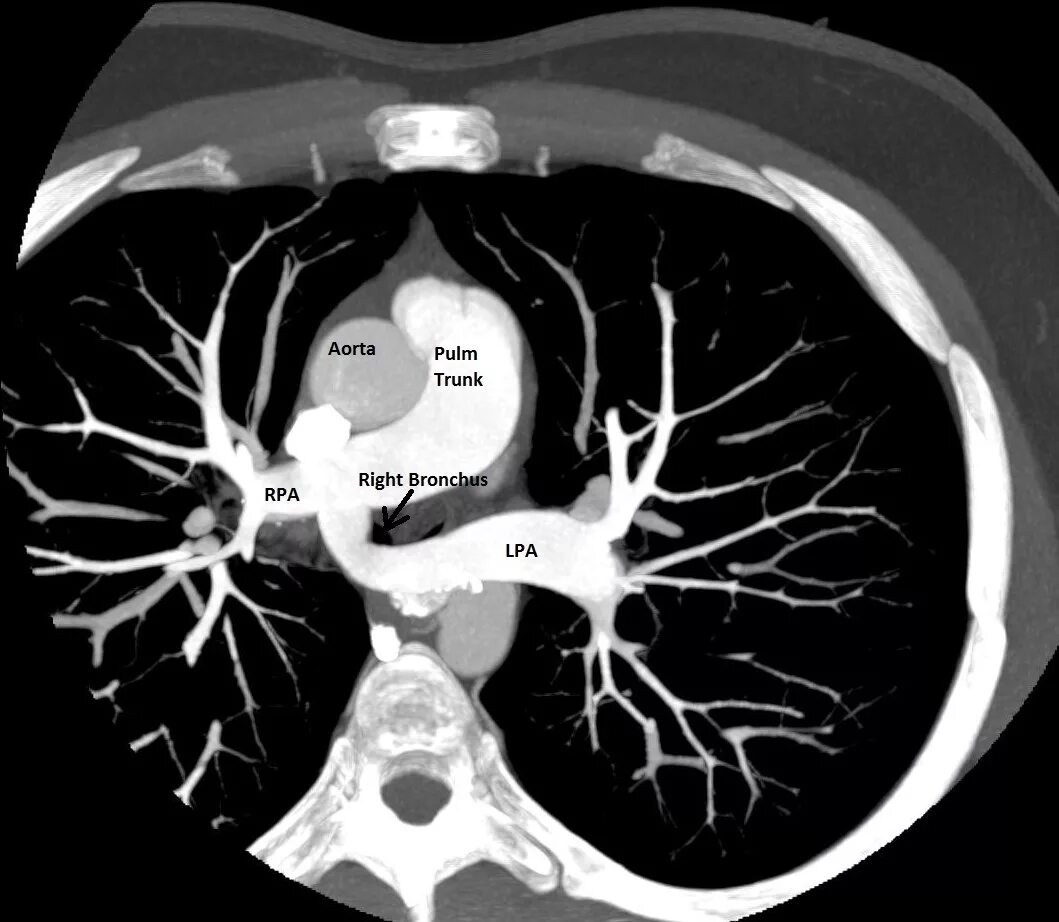

Легочный ствол на кт